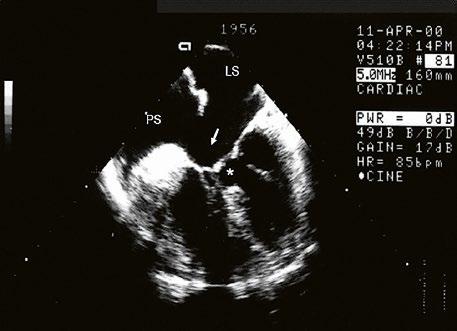

Obr. 45.15 Přechodná forma atrioventrikulárního septálního defektu, TEE, čtyřdutinová projekce. V dolní části síňového septa je mezi pravou síní (PS) a levou síní (LS) velká komunikace typu ostium primum (označená šipkou), původní komorová složka defektu (označená hvězdičkou) je částečně spontánně uzavřena závěsným aparátem trikuspidální chlopně.